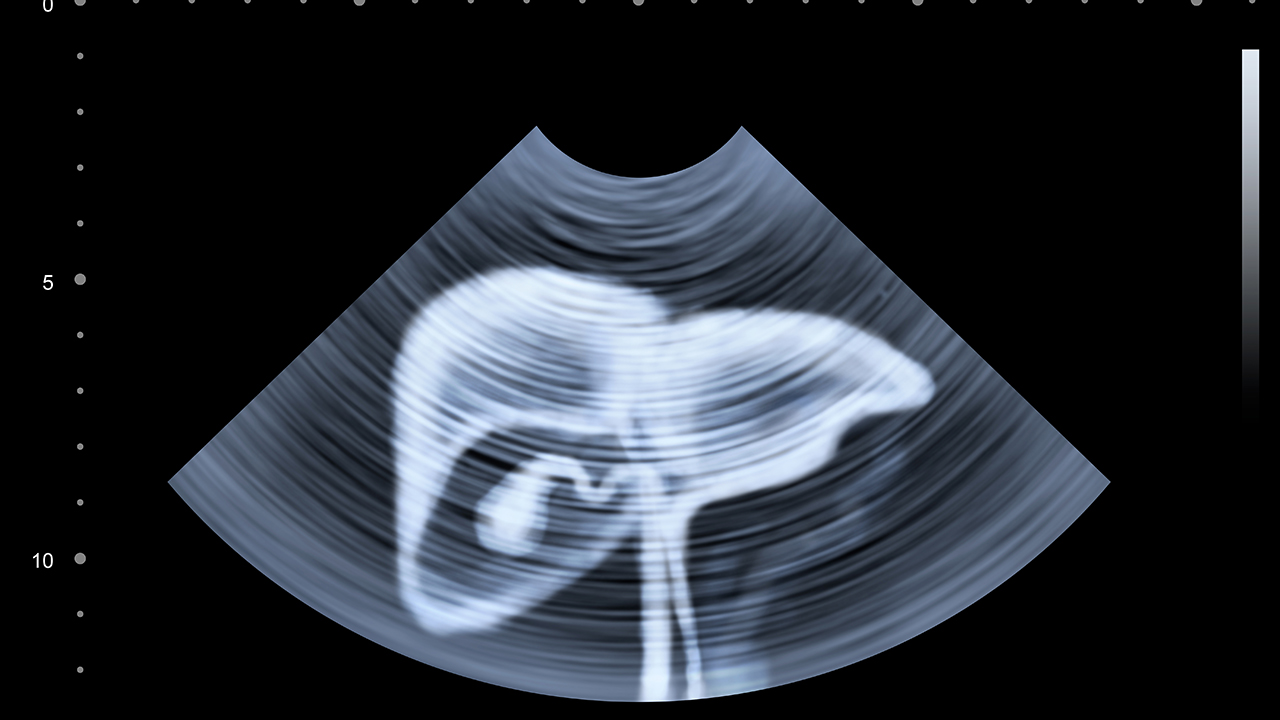

山东第一医科大学第一附属医院是山东省重要的医疗教学科研基地,其肝胆外科在肝癌诊疗方面具有较强实力。医院拥有数字减影血管造影系统、超声引导系统等设备,能够开展肝癌介入治疗。医院还注重肝癌的早期筛查和诊断,提高治果。

肝癌的预防与健康管理至关重要。建议高危人群定期进行肝脏超声和甲胎蛋白检查,做到早发现、早治疗。日常生活中应避免酗酒,注意饮食卫生,避免食用霉变食物。乙肝病毒携带者应定期监测肝功能,必要时进行抗病毒治疗。保持良好的生活习惯,适量运动,增强免疫力,有助于降低肝癌发病风险。一旦确诊肝癌,应及时到正规医院接受规范治疗,避免延误病情。